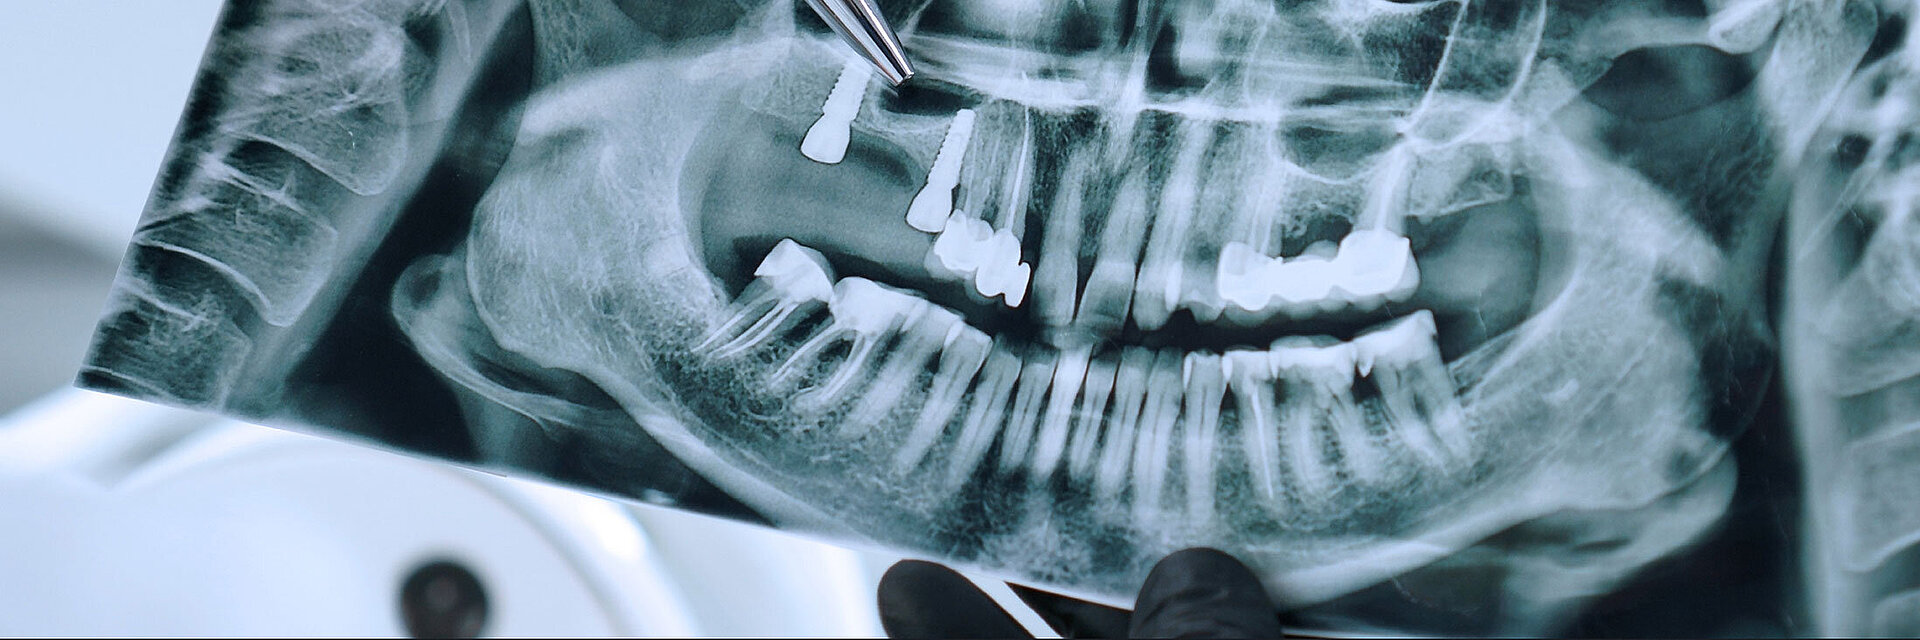

Peri-implant mucositis can be defined as an inflammatory lesion of the soft tissues (mucosa) surrounding the dental implant. Peri-implantitis is an inflammatory lesion of the mucosa affecting the supporting bone (crestal bone) with crestal bone loss and loss of osseointegration. Derks et al. report a prevalence of 43% for peri-implant mucositis and Jepsen et al. estimate that the prevalence of peri-implantitis could reach 22% (Figs. 1, 2).2,3 Peri-implantitis is usually accompanied by crestal bone loss (Fig. 3) and soft tissue changes in the peri-implant sulcus, which can be diagnosed by an increase in bleeding on probing (BOP) more than 5mm over previous examinations and/or suppuration8 (Fig. 4). Also excess of residual cement might contribute to crestal bone loss (Fig. 5).7

The underlying inflammatory processes are still not completely understood. However, increasing evidence shows that the host and the peri-implant conditions might play a pivotal role in the development of peri-implantitis (Figs. 1, 2).2,3